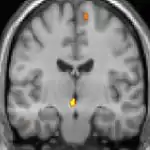

Positron emission tomography (PET) scans indicate the brain areas which are activated during attack only, compared to pain free periods. These pictures show brain areas that are active during pain in yellow/orange color (called "pain matrix"). The area in the center (in all three views) is specifically activated during CH only. The bottom row voxel-based morphometry (VBM) shows structural brain differences between individuals with and without CH; only a portion of the hypothalamus is different.[36]